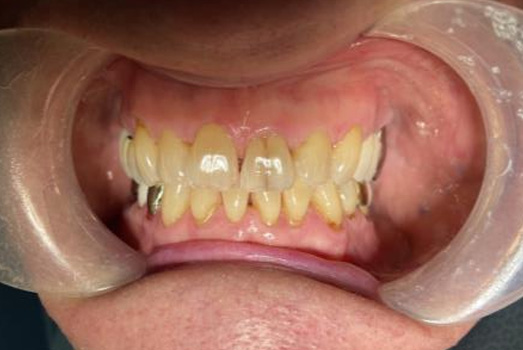

Final Intraoral Photographs